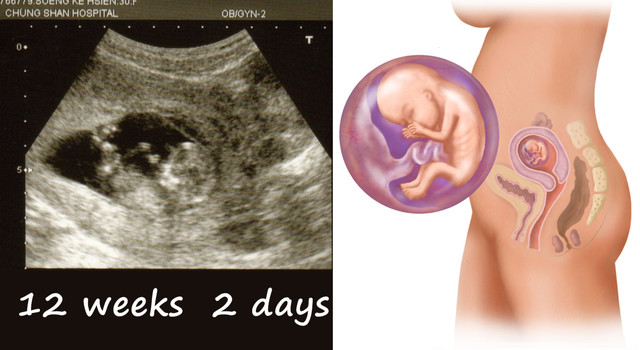

divide懷孕12週症狀:孕婦生理變化害喜現象已近尾聲,但偶爾還會感到頭暈、頭痛與疲倦,便秘的現象將越來越嚴重。 懷孕12週胎兒大小:胎兒身長可達到65厘米,現在寶寶已經初具人形。 divide 妳已經懷孕第12周了 懷孕第12周的時候胎兒身長可達到65厘米,現在寶寶已經初具人形。妊娠12週ごろ~ ・指しゃぶりをする(私は定期健診のモニターで確認できました。 ) ・羊水を飲む ・おしっこをする 妊娠15週ごろ~ ・まぶたの下で目が動く お母さんが気づいてないだけで赤ちゃんはお腹の中でさまざまな動きをしています。開始關注這則討論 關注 探索更多 熱門關鍵字 副食品 奶粉

胎動 12週 妊娠12週目エコー写真と胎児の大きさと・流産の壁の実際 妊娠 妊娠12週目は胎動や赤ちゃんの性別はまだ分からない 胎動を感じるのはまだ先ですが、子宮の中では、赤ちゃんの動きもだいぶ激しくなってきました。內容編輯/Vera Chen 我們可以浪漫地把胎動次數多寡,想成是胎兒的「語言」,它傳遞出寶寶健康狀況、回應互動,甚至有人認為跟未來性格息息相關,你知道該如何計算胎動次數嗎? 第一次感受到胎動是何時? 懷孕滿4個月後(初產婦約17週左右/ 經產婦約15、6週左右),胎兒在子宮內所有的活動12 週時,胎兒已經會握拳,身長約 7 ~ 8 公分,但這時仍然無法感覺到胎動,到 16 ~ 17 週時,胎兒約 0 公克,較敏感的媽媽或是子宮較軟的媽媽就可以感覺到胎動,但是這時候的胎動力微弱,還不會出現肚皮明顯隆起或突出的情況, 週後,四肢和全身已經可以做踢、伸、握拳或翻身等,到 25